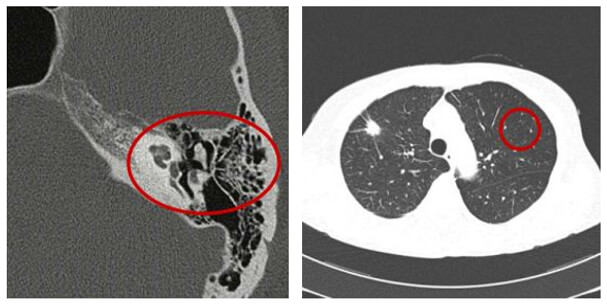

Spatial Resolution / Contrast

In areas such as the inner ear and the thorax, there are large differences in densities between very close structures. Using a wide window, there will be little visible noise in the image. Thus, the delivered dose could be low.

Low Contrast Resolution

The ability to distinguish between tissues with slight contrast differences is known as low contrast resolution. This is one of the advantages of CT and conventional radiography.